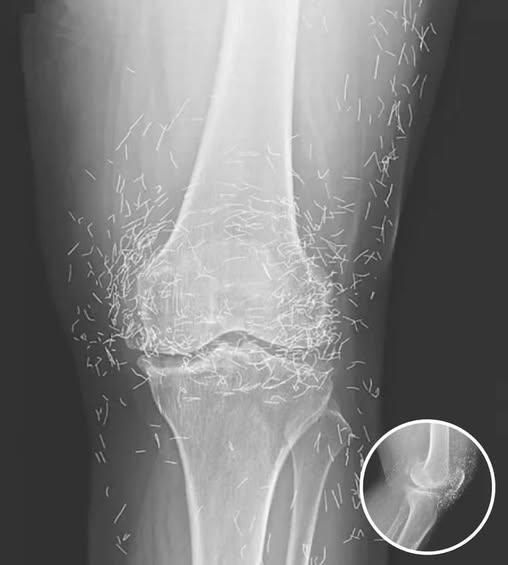

The intersection of ancient tradition and modern diagnostic medicine rarely produces an image as startling as the one that recently captivated the global medical community. When a 65-year-old South Korean woman presented herself for a routine examination to address chronic, debilitating joint pain, her physicians expected to see the standard markers of age-related wear and tear. Instead, as the X-ray film developed, they were met with a sight that seemed more akin to a piece of intricate jewelry than a human anatomy. Embedded deep within the soft tissue and synovial spaces of her knees were hundreds of tiny, shimmering gold needles, perfectly preserved in a geometric display of alternative intervention. This case, later documented in the New England Journal of Medicine, has ignited a fierce debate over the boundaries of traditional healing and the hidden risks of permanent “embedded” therapies.

Beyond the immediate risk of infection, these “shimmering” knees present a massive obstacle to modern diagnostic technology. Metal of any kind is notorious for creating “artifacts” on an X-ray or CT scan—streaks of white light that obscure the very anatomy a doctor is trying to see. In this woman’s case, the sheer density of the needles made it nearly impossible for physicians to accurately assess the current state of her osteoarthritis. The very “cure” she sought had created a visual shield that hid the progression of her disease.

However, the most life-threatening risk involves the gold standard of modern diagnostics: the MRI (Magnetic Resonance Imaging). An MRI machine is, essentially, a massive and incredibly powerful magnet. If a patient with hundreds of metal needles embedded in their joints were to enter an MRI suite, the results could be catastrophic. The magnetic field can exert enough force to cause the metal fragments to migrate or vibrate violently within the tissue. This could lead to internal hemorrhaging, the puncturing of vital blood vessels, or severe nerve damage. In a medical emergency where an MRI might be the only way to save a life, these permanent acupuncture needles could effectively bar a patient from receiving life-saving care.